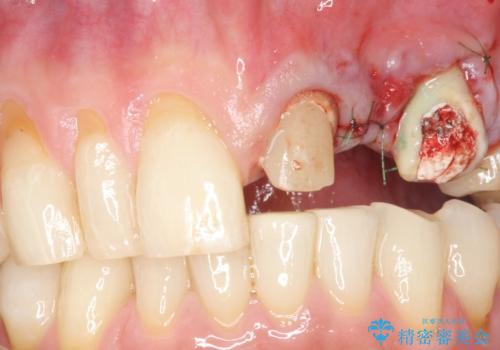

歯を牽引し健全歯質を歯肉縁上まで引き上げ、歯の保存を試みることにしました。

歯の牽引後、ブリッジの仮歯で保定しながら歯肉・骨の治癒を待ったのち、ブリッジによる補綴を行いました。

根の長さが短くなるためブリッジの支台歯としては弱いこと、長期的予後は不明なことをご理解頂いた上で治療を行いました。

根管治療はご希望されず行っておりません。